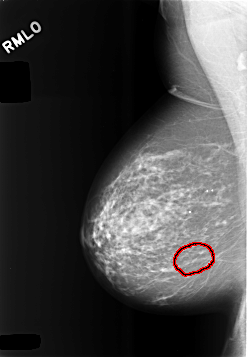

C_0473_1.RIGHT_MLO

RIGHT_MLO LINES 5712 PIXELS_PER_LINE 3968 BITS_PER_PIXEL 12 RESOLUTION 50 OVERLAY

FILE: C_0473_1.RIGHT_MLO.OVERLAY

TOTAL_ABNORMALITIES 1

ABNORMALITY 1

LESION_TYPE CALCIFICATION TYPE FINE_LINEAR_BRANCHING DISTRIBUTION LINEAR

ASSESSMENT 4

SUBTLETY 3

PATHOLOGY BENIGN

TOTAL_OUTLINES 1

BOUNDARY